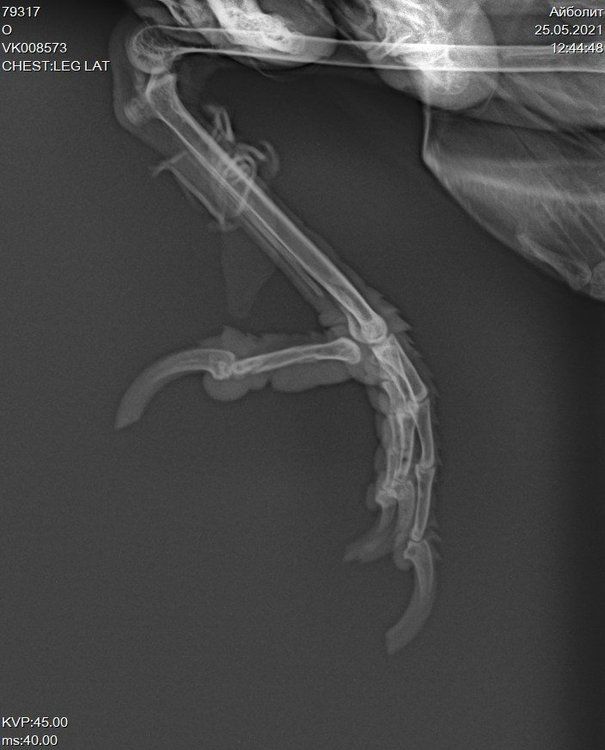

Получила выписку и рентген. Прикрепляю последние снимки.

VK008573_1.jpg

VK008573_2.jpg

VK008573_3.jpg

VK008573_4.jpg

На рентгене нет ли перелома заднего пальца?

@fishka врач не увидела, но мне увиделся перелом. И не на рентгене, а в живую. Палец гнется не в ту сторону :(